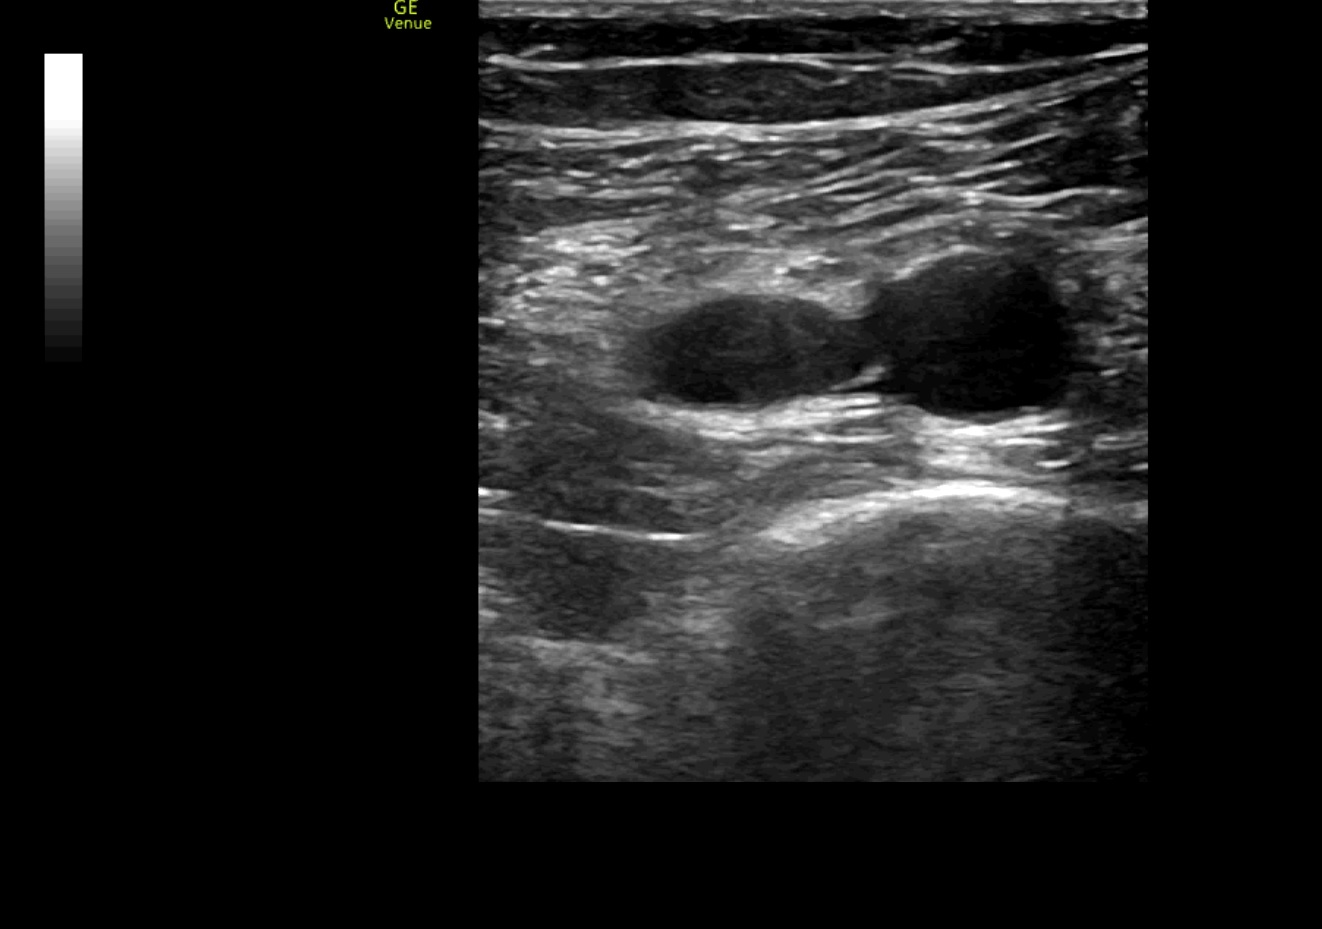

Se realiza ecografía clínica de vasos en miembros inferiores objetivándose un trombo en vena poplítea derecha y ecocardioscopia con dilatación de ventrículo derecho.

La ecografía clínica puede ser una herramienta de gran utilidad para el diagnóstico de trombosis venosa profunda, al igual que para poder determinar importantes factores pronósticos de un tromboembolismo pulmonar, como en este caso la sobrecarga de cavidades derechas, permitiendo una aproximación diagnóstica de forma rápida antes de realizar pruebas complementarias adicionales.